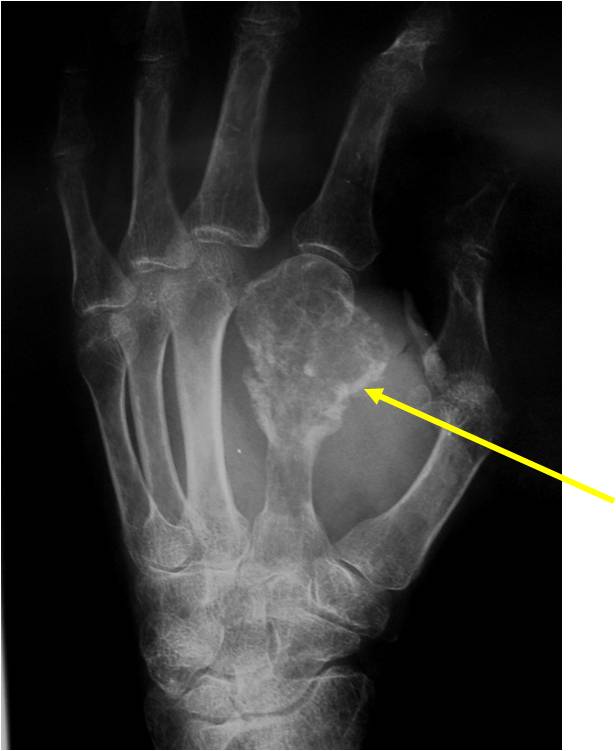

- Localized, radiolucent defect usually with punctate calcifications

- Calcifications are typical but not always present

- Matrix may demonstrate various degrees of calcification

- Calcifications are stippled, punctate, popcorn like calcifications and “Ring and Arc” calcifications

- Cartilage tumors grow in a lobular manner. The perimeters of the lobules undergo

- enchondral ossification that may calcify. If the entire perimeter of the lobule calcifies it appears

- radiographically as a “Ring”. If a portion of the perimeter of a lobule calcifies it forms an “Arc” on

- an X-ray.

- Cortex may be scalloped and thinned in the phalanges

- Geographic lytic lesion

- Expansile remodeling with thinned cortex

- Chondroid matrix with calcifications in majority of tumors

- Enchondral ossification may occur around periphery of lobules and when calcified appear as “Rings and Arcs” on X-rays